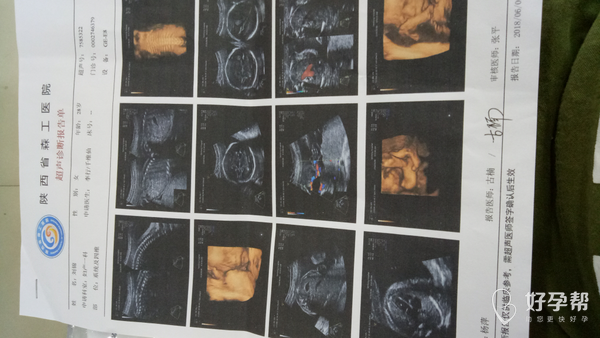

麻烦给看看,这是今天做的四维结果,

你好发育数值都挺好的,那个亚麻酸不是必须要吃的,平时注意均衡营养就可以。

检查结果都正常吗?医生让吃亚麻酸DHA,必须要吃吗?还有要注意的吗?